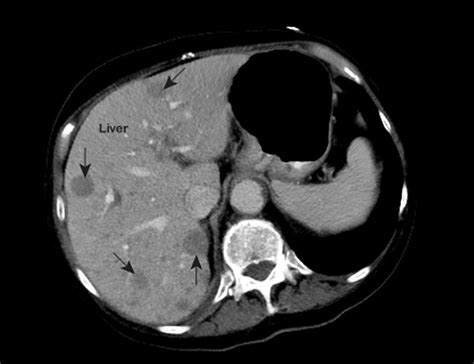

Abdominal CT Scan Provides detailed cross-sectional images to identify lesion size and location.

💡 Note: While imaging is highly effective, not all liver lesions are cancerous; some may be benign cysts or hemangiomas, which is why clinical correlation is always necessary.